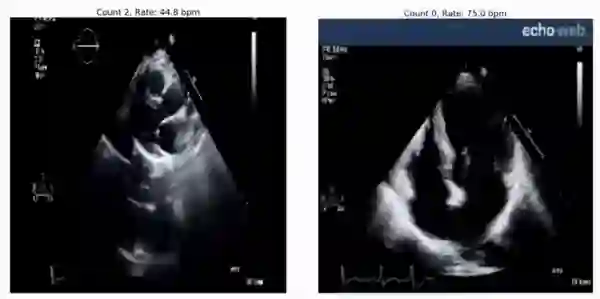

RepNet 可用于评估来自超声波心动图视频的心率,即便它在训练期间并未见过这样的视频:

预测心率: 45 bpm(左)和 75 bpm(右)。 实际心率分别为 46-50 bpm 和 78-79 bpm。 RepNet 对不同设备的心跳速率预测非常接近设备实际测得的心跳速率